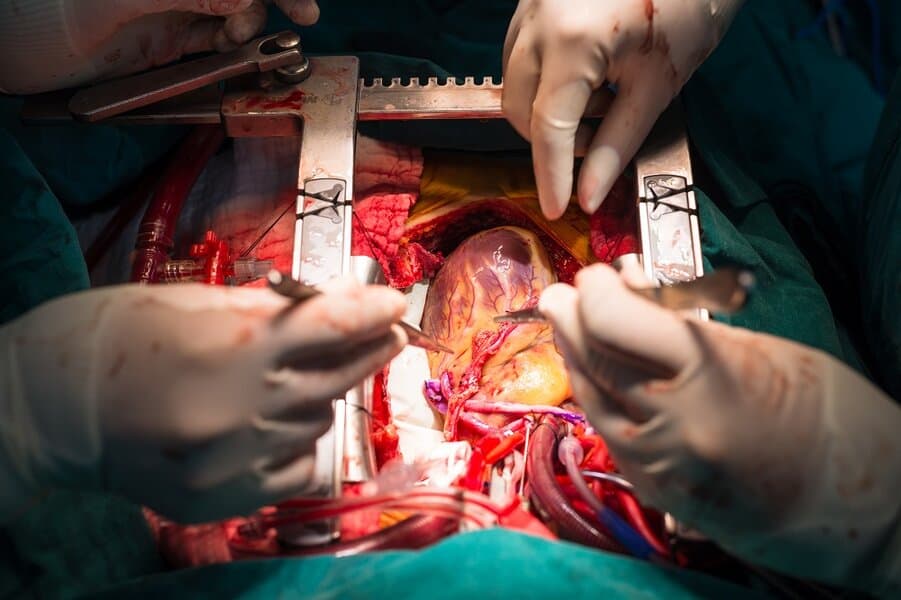

Coronary artery bypass surgery is one of the most common open heart surgeries. The surgical procedure treats a buildup of plaque in the heart’s arteries. Better known as coronary artery disease, the surgery increases life expectancy, eases chest pain, and slows the progression of the disease.

Open heart surgery requires the surgeon to make a significant cut in the chest to open the rib cage. During the surgical procedure, the surgeon takes healthy arteries or veins from other body parts to circumvent the narrowings in the heart arteries. Thus, it restores blood supply to the deprived area. Complications from the surgery include heart failure, stroke, renal dysfunction, and wound infections.

Surgery always involves risks, but they increase when it’s an open heart surgery. An aortic dissection is a severe injury to the innermost layer of the aorta. Symptoms include sweating, lightheadedness, and intense back or chest pain. Sometimes the blood supply decreases to other organs, causing a stroke.

Thoracic aortic dissection repair is required to ease pain and prevent death. The procedure is risky, increasing the chances of a stroke, but this type of emergency surgery is required to fix a damaged aorta and rebuild the blood vessel.

12. Cardiopulmonary Bypass

A cardiopulmonary bypass is a risky procedure that can end in death. Also known as CPB, the method involves a machine taking over the function of the lungs and heart during surgery. It supports the circulation of oxygen and blood throughout the body, so as you can imagine there are several risks involved with the procedure.

Surgeons will only use the machine during the surgery to avoid permanent damage. Also known as the heart-lung machine, other complications include acute respiratory distress syndrome, aortic dissection, and protamine reaction.